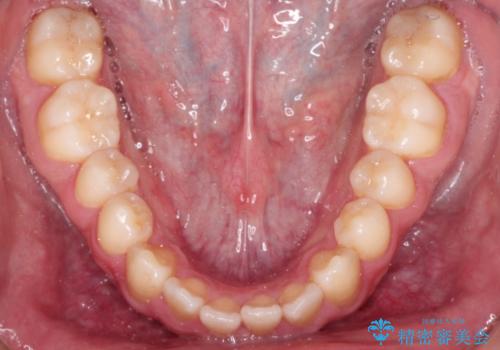

前歯が反対にかんでいる インビザラインとワイヤーを組み合わせた矯正治療

- 前歯が正常とは反対にかんでいるとのことで、来院されました。

マウスピースのみでの治療も可能でしたが、治療期間がもう少し延長していた可能性があります。